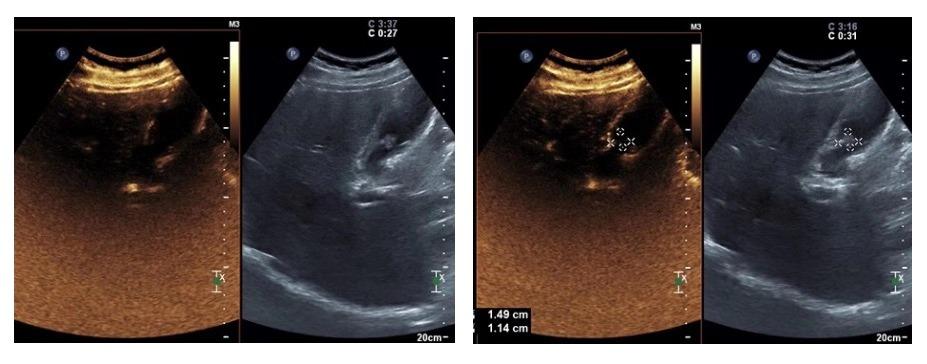

患者男,49岁,2年前体检发现“胆囊息肉”,无疼痛、发热等症状,后定期复查。2019.12彩超复查示:胆囊占位,较前明显增大。欲给予进一步治疗,遂至我院,以“胆囊占位”入住我科。例行超声检查,胆囊内可探及一高回声团,大小约16.2mmx11mm,后伴彗尾,不随体位移动。影像提示:胆囊占位(考虑腺瘤)。

进行胆囊脂餐实验,让患者口服油腻食物,半个小时后再行超声检查,通过前后胆囊的大小变化来判断胆囊的收缩功能。

由此可得,该患者胆囊收缩率约为80%,胆囊收缩功能正常,具有保留胆囊的意义。(一般情况下缩小50%以上,可视为胆囊收缩功能正常)